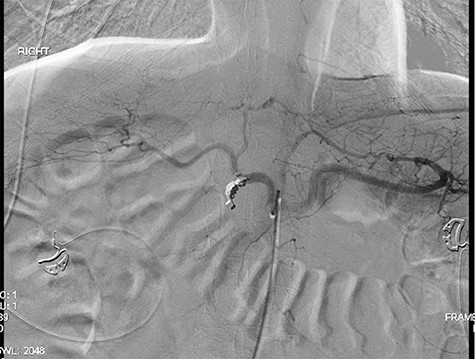

A 56-year-old African American male presented in 2015 with abdominal pain, with associated melena and hematochezia. The patient has a history of chronic back pain for which he takes 600 mg ibuprofen daily, alcohol abuse, tobacco use and a previous GI bleed in 2011, which necessitated 6 units (U) of packed red blood cells (PRBCs) and emergency therapeutic endoscopy. The patient was found to be hypotensive to 76/56 mm Hg, and hemoglobin (Hgb) was found to be 9.4 g/dl, from a previous baseline of 10.6 g/dl. His rectal examination was guaiac positive. A repeat Hgb was found to be 6.5 g/dl. The patient was given 3 U of PRBC and an emergency endoscopy was performed. On endoscopy, the patient was found to have a 6 cm gastric ulcer with an associated vessel underneath of a large clot. Due to the high risk nature of the bleed, it was felt by the gastroenterologist that the patient should undergo an endovascular angioembolization (Fig. 1). The patient was brought to the Interventional Radiology Suite for the procedure. The patient’s right common femoral artery was accessed and the celiac trunk was selected. A subselective common hepatic arteriogram was performed, which demonstrated active extravasation arising from the proximal aspect of the GDA. The GDA was then coil embolized both proximal and distal to the site of bleeding using five microcoils. Repeat arteriogram demonstrated no further opacification of the GDA and no further extravasation (Fig. 2).

Demonstrating coil embolization of the GDA with no opacification